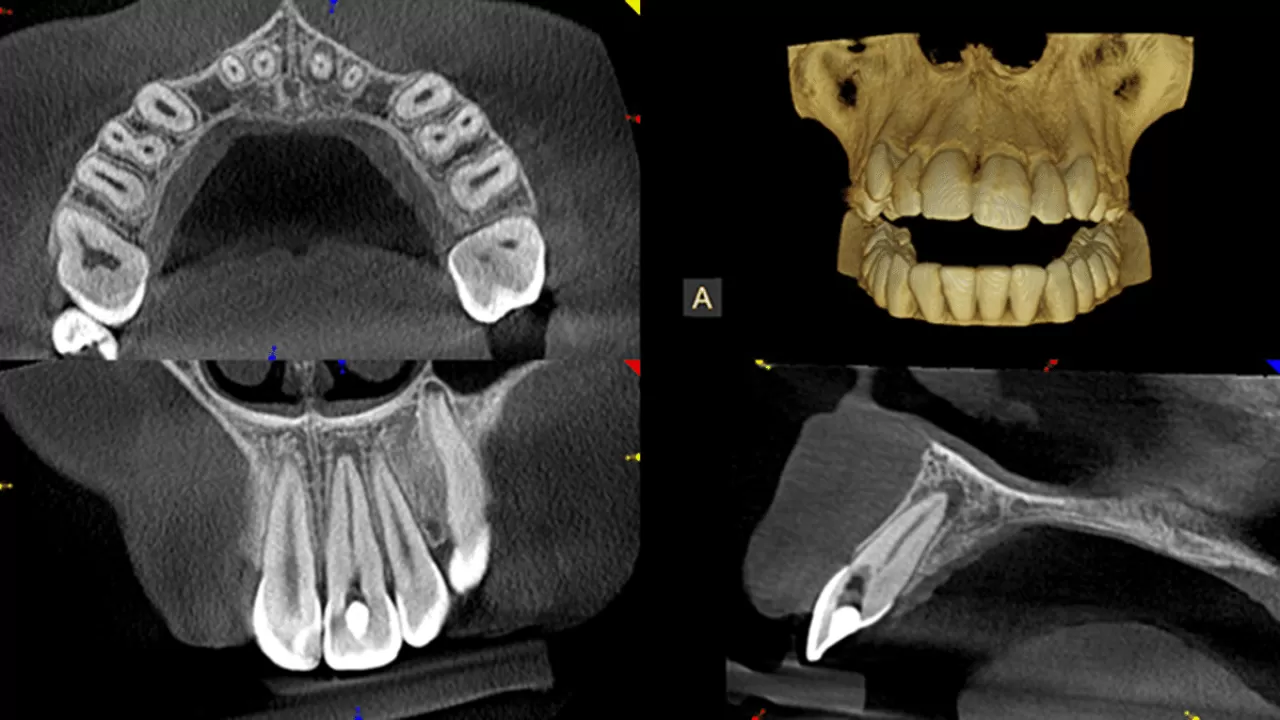

3D snimanje zuba (CBCT – Cone beam CT) najsuvremenija je dijagnostička metoda kojom stomatolog dobiva najprecizniji i najdetaljniji uvid u stanje kostiju, zuba i korijena gornje ili donje čeljusti i na taj način ima mogućnost vizualizacije snimaka po presjecima u sve tri dimenzije.

Stomatologu je omogućena jednostavna analiza s brojnim dodatnim alatima za obradu dobivene radiološke slike te detaljno planiranje implanto-protetske terapije.